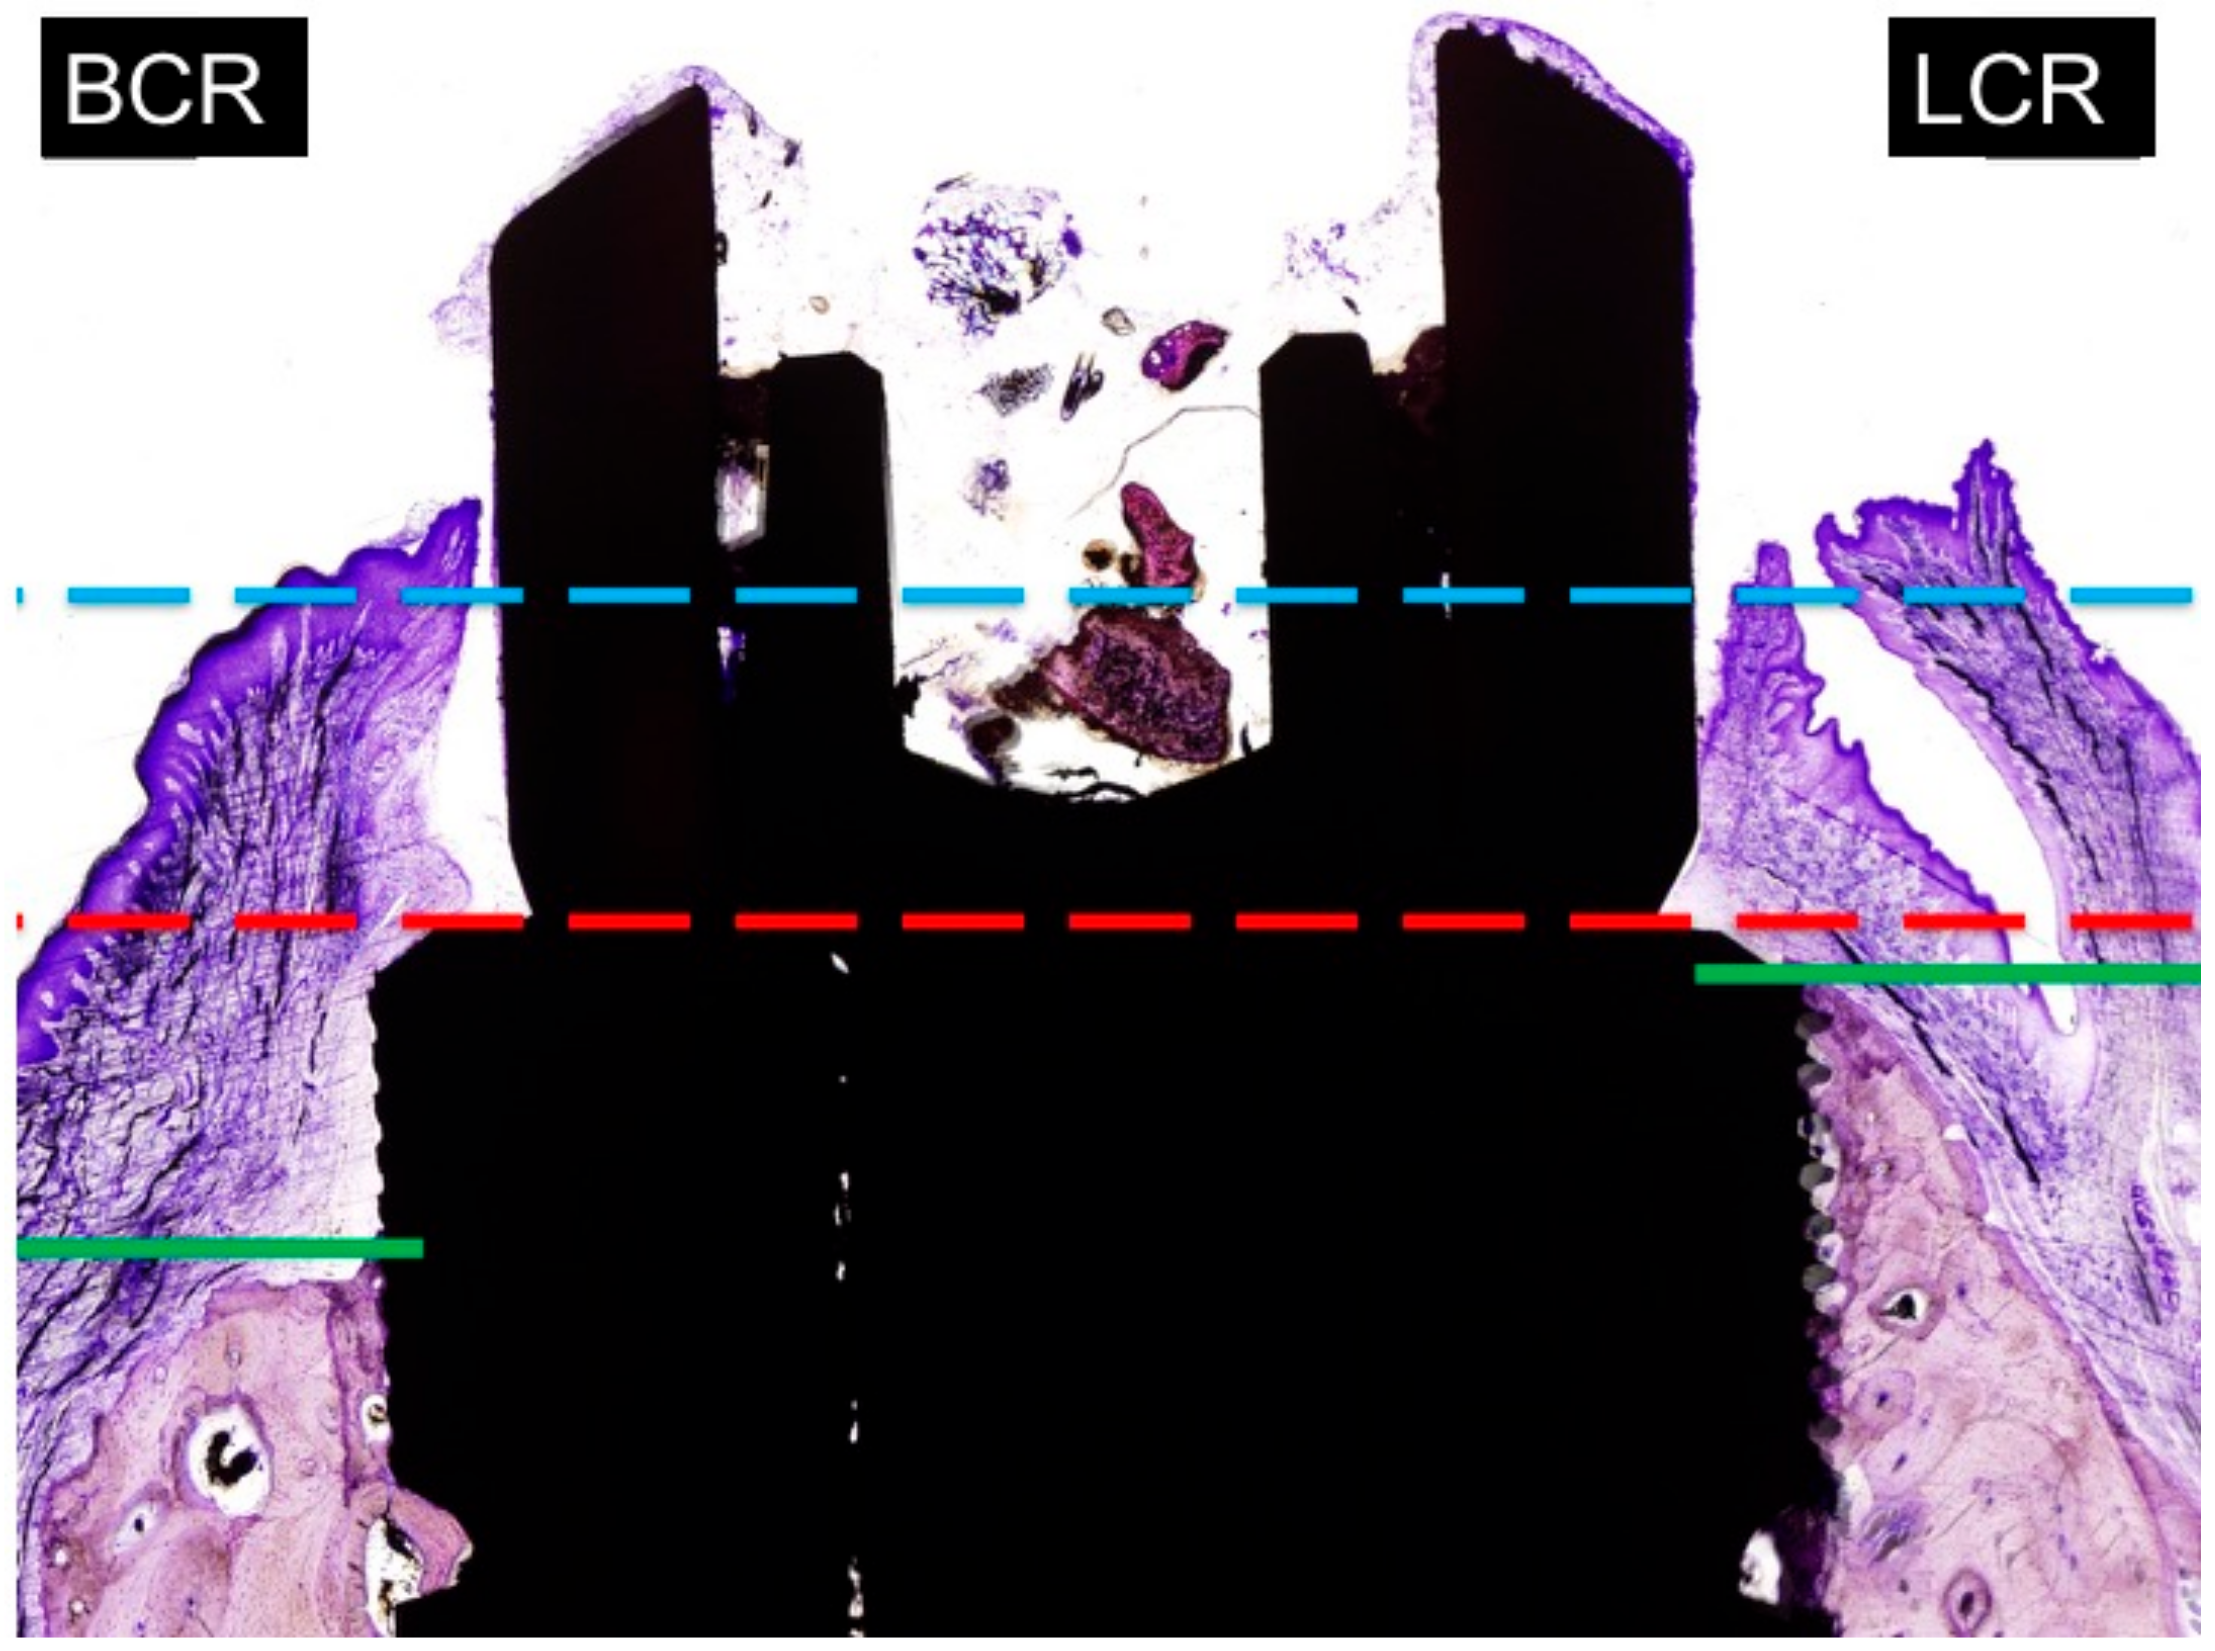

4.4. Marginal Bone Loss

The distance from the implant platform to the highest portion of the buccal and lingual bone. The measurements of buccal and lingual crests bone loss were expressed in millimetres (Figure 7). To facilitate differentiation between native and newly formed bone, blue and light blue chromaticity were enhanced by digital processing. Buccal bone wall resorption in relation to the lingual bone wall was expressed as a linear measurement in millimeters (relative measurement).

Figure 7.

Measurements of marginal bone loss: BCR: buccal crest resorption (distance from the top of the implant shoulder to the first BIC in the buccal crest side. LCR: lingual crest resorption (distance from the top of the implant shoulder to the first BIC in the lingual crest side).